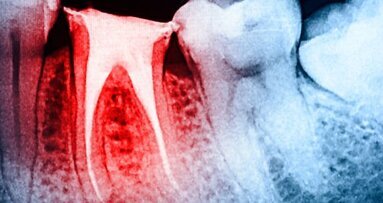

WUHAN, China: Utilizando um instrumento rotativo que é mais eficaz na preparação do canal radicular é crucial para o sucesso do ...